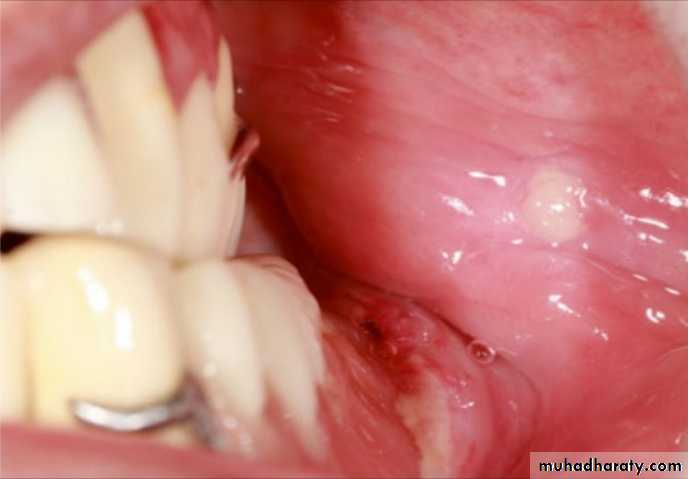

With the use of monoplane posterior artificial teeth, this problem is seen more often because the teeth are arranged with no horizontal overlap.The cheeks may be trapped between the

occluding surfaces of the posterior artificial teeth, and painful ulcerations may be seen in patients wearing RPDs with inadequate posterior teeth overlap

The cheeks are trapped between the occluding surfaces of the posterior artificial teeth and painful ulcerations may be seen .

To overcome the problem of insufficient overlap, the posterior teeth might be gently rounded and reduced in size buccally or all the posterior teeth may be reduced buccally to move away from the soft tissues.